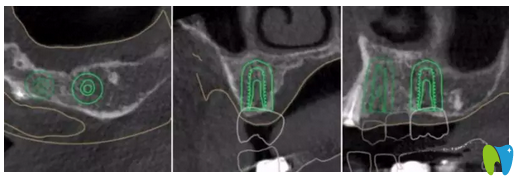

CT片顯示14區(qū)缺牙間隙較狹窄

CBCT顯示:14區(qū)缺牙間隙較狹窄,模擬植入后,近遠(yuǎn)中距臨牙安 全距離不足1.5mm;其余缺牙區(qū)骨質(zhì)及骨量的情況,以及距離上頜竇底高度均基本滿足種植要求。缺牙區(qū)咬合高度基本滿足后期修復(fù)要求。

▲ 患者左上6牙位模擬種植圖

▲ 患者左上4牙位模擬種植圖